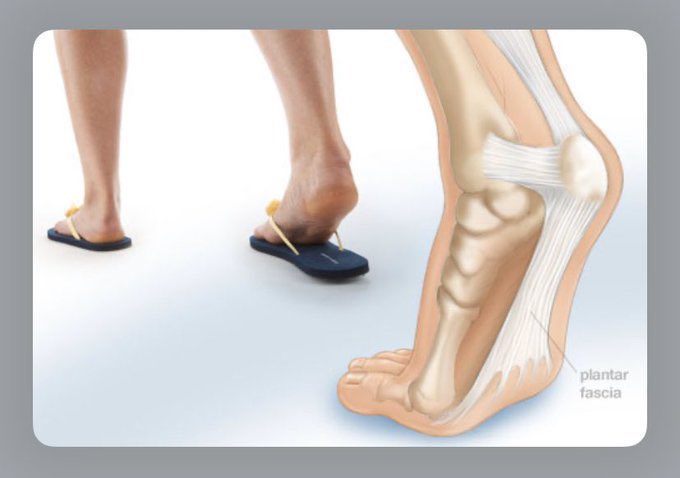

♦️إرتداء أحذية غير مناسبة لا تدعم قوس القدم مثل الصنادل/ألجزم الفلات/كعب عالي

♦️إرتداء أحذية غير مناسبة لا تدعم قوس القدم مثل الصنادل/ألجزم الفلات/كعب عالي